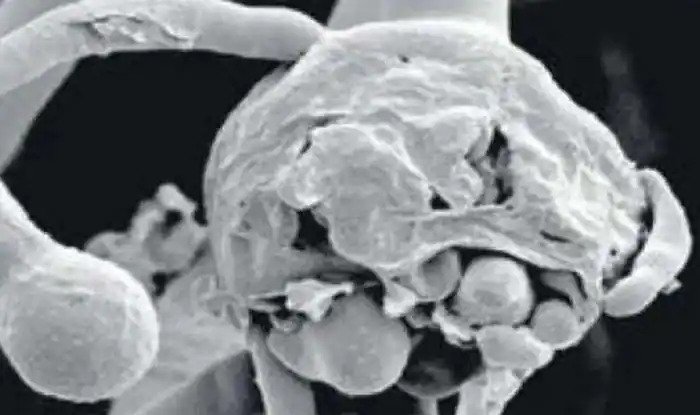

मुंबई, 18जून। देश में कोरोना संक्रमण से उबरने के बाद फंगस बहुत बड़ी समस्या बनी हुई है। ब्लैस फंगस, व्हाइट, येलों के साथ- साथ अब ग्रीन फंगस नें भी भारत में कदम रख दिया है। ब्लैक फंगस के अबतक कई डरावने मामले सामने आ चुके हैं और अब नया मामला मुंबई से सामने आया है। यहां ब्लैक फंगस के शिकार तीन बच्चों की आंख निकालनी पड़ी है. जानकारी के मुताबिक तीनों बच्चे कोरोना से रिकवर हो चुके थे, लेकिन बाद में ब्लैक फंगस के शिकार हो गए।

तीनों का इलाज मुंबई के एक निजी अस्पताल में कराया जा रहा था। इन बच्चों की उम्र 4,6 औऐर 14 वर्ष है। डॉक्टर्स के मुताबिक 4 और 6 साल के बच्चे में डायबिटीज के लक्षण नहीं हैं, जबकि 14 साल के बच्चें में डायबिटीज के लक्षण मिले हैं। वहीं एक 16 साल की लड़की भी है जो कोरोना से रिकवर होने के बाद डायबिटीज का शिकार हो गई और उसमें ब्लैक फंगस पाया गया है।

अस्पताल के डॉ. जेसल सेठ के मुताबिक ब्लैक फंगस के अस्पताल में दो मामले सामने आए हैं, जिनमें दोनों ही बच्चे नाबालिग थे. 14 साल की बच्ची जो डायबिटीज का शिकार थी. उसकी हालत ठीक नहीं थी और अस्पताल में भर्ती होने के 48 घंटे के भीतर ब्लैक फंगस के लक्षण दिखने लगे. इसके बाद लड़की की आंख को हटाना पड़ा।

डॉक्टर्स के मुताबिक 16 साल की बच्ची के पेट में ब्लैक फंगस था. हालांकि वह बाद में रिकवर कर गई वहीं 4 और 6 साल के बच्चों का इलाज निजी अस्पताल में किया गया और अगर बच्चों की आंख न निकाली जाती तो उनकी जान बचाना काफी मुश्किल हो जाता।